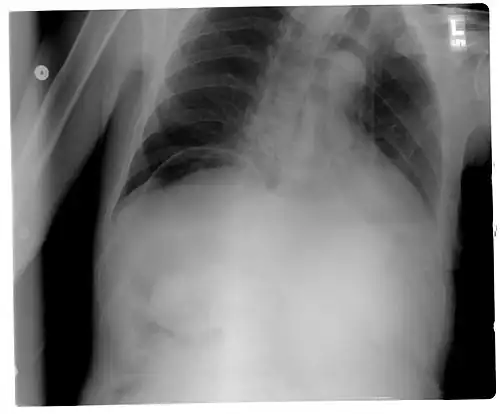

Another pneumoperitoneum on chest X-ray. -

Pneumoperitoneum seen on X-ray with the patient lying on his left side. -